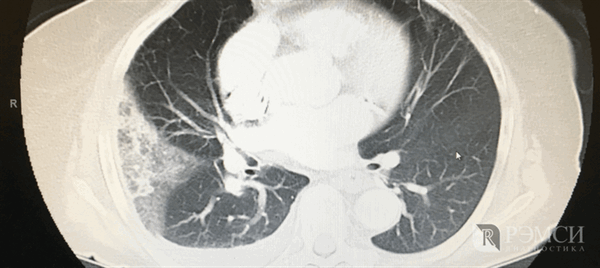

Фото томографии грудной клетки

Расшифровка снимков происходит в тот же день. Полученные изображения анализирует врач-рентгенолог, который и выдает заключение. Определить верный диагноз непросто, ведь среди нескольких десятков оттенков черного, серого и белого необходимо вычленить несоответствующий норме и интерпретировать результат. Представим Вашему вниманию несколько фото томографии грудной клетки:

КТ без контраста у пациента с интерстициальным заболеванием легких в анамнезе и трансплантацией правого легкого показывает суженный участок анастомоза правого бронха (красная стрелка). Собственное левое легкое уменьшено в размерах, с признаками бронхоэктазов, бронхиолоэктазов (черная стрелка). Сужение центрального дыхательного пути на выдохе у трансплантированного легкого (синяя стрелка).

Выпот (красные стрелки) в обеих плевральных полостях.